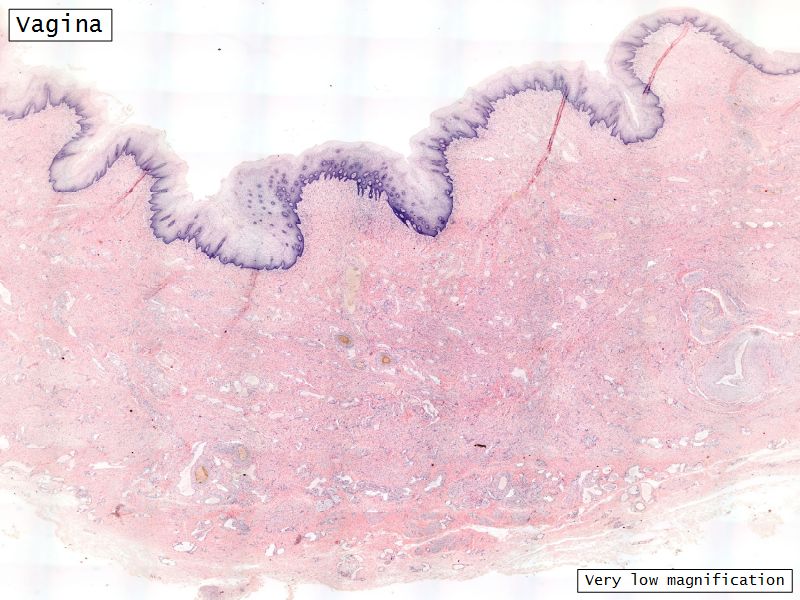

Vagina

Slide 90

Vagina

- Fibromuscular tube with 3 layers

- Inner mucosa

- Middle muscle layer

- External adventitia

Fibro = fibrous tissue

Muscular = muscle tissue

Tube = epithelium

Mucosa

- Epithelium

- Thick stratified squamous nonkeratinized

- Lamina propria

- Fibroelastic connective tissue

- Rich in elastic fibres

- Contains lymphoid elements

- Deep portion highly vascular

- No glands

Muscle layer

- Thin inner circular

- Thick outer longitudinal

- External orifice ring of skeletal muscle

Adventitia

- Fibroelastic connective tissue

- Fixes onto surrounding structure

- Blood vessels and nerves